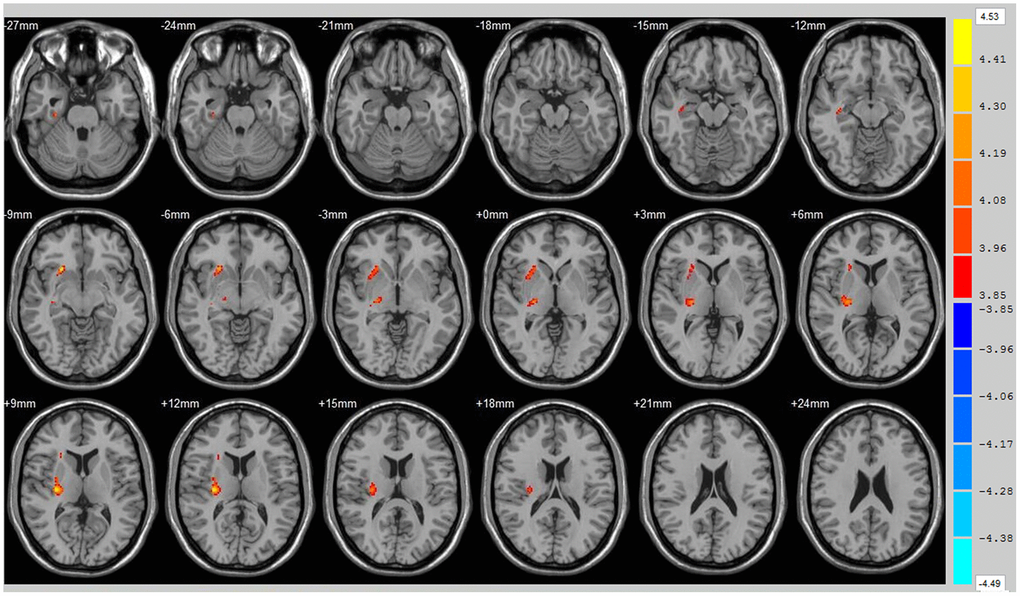

Using the whole brain analysis, we found that 1 week after ICH, patients displayed lower FA values in two brain clusters that included the ipsilateral temporal lobe, frontal lobe, insula, lenticular nucleus, putamen, caudate nucleus, hippocampus and thalamus than did the controls (Figure 1 and Supplementary Table 1). Two clusters with decreased FA values were also observed at week 12 (Figure 2 and Supplementary Table 2). Moreover, 12 weeks after ICH, six clusters (ipsilateral frontal lobe, lenticular nucleus, caudate nucleus, putamen, globus pallidus, and the contralateral parietal lobe, temporal lobe and hippocampus) exhibited higher FA (Figure 3, orange and Supplementary Table 3) while two clusters (ipsilateral limbic lobe, posterior cingulate gyrus and hippocampus) exhibited lower FA than at week 1 (Figure 3, blue and Supplementary Table 4).

Figure 2. Brain areas with decreased FA value of ICH patients at 12th w. Orange means brain areas with decreased FA value of ICH patients compared with control group at 12th w, Threshold=3.8495.